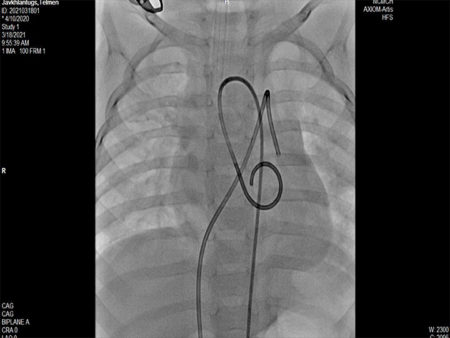

新型コロナウイルスの影響により、ハートセービングプロジェクトがモンゴルに出向いて健診・治療・教育活動が行い得ないため、オンラインで症例紹介、設定されたテーマに沿った講義を行うことを目的に、本年は年に3回のオンライン学会を開催することになりました。その第一回目が5月15日(土曜日)日本時間午後19時(モンゴル時間午後18時)から行われ、参加総数40名となる大盛況の会となりました。第1回のテーマは「大動脈弁縮窄症」、モンゴルからはモンゴル国立母子保健センターのボロルマー先生、バヤルマー先生、ナランツァツラル先生、ウンドラル先生、バトウンドラル先生、ワンチンドルジ先生による心カテーテルの3症例の紹介、日本からは愛媛大学病院の檜垣高史先生、河本敦先生、高田秀美先生によるCoAカテーテルインターベンションについての講演がありました。